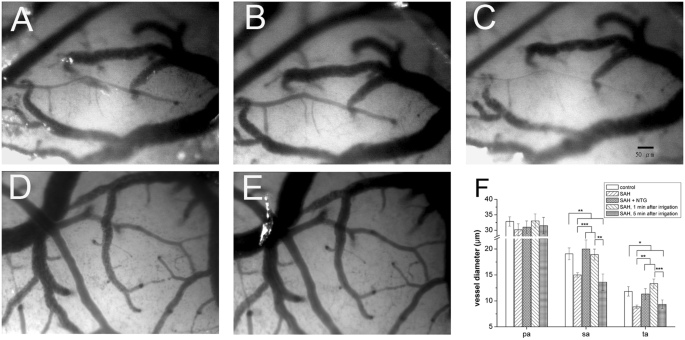

Vaosconstriction of small arterioles after subarachnoid hemorrhage (SAH) was reversible. The microcirculation on the brain surface of rats after craniotomy was examined 24 hours after experimental SAH, as detailed in Materials and Methods. (A,D) Marked vasoconstriction was observed in arteriole 24 hours after SAH. (B) The vasoconstrictive effect was alleviated by normal saline irrigation initially, but rebound vasoconstriction noted 5 min after irrigation (C). (E) The vasoconstrictive effect was reversible by application of nitroglycerin (NTG). (F) Quantitatively, the diameters of the sa and ta were smaller in the SAH group than in the control group. The size of the primary arterioles (pa) was similar in both groups. The vasoconstrictive effect could be alleviated by normal saline irrigation or NTG application. *p < 0.05, **p < 0.01, ***p < 0.001.

The constricted arterioles dilated immediately after normal saline irrigation [diameters 1 min before and after irrigation: sa (15.0 ± 0.48 vs. 18.9 ± 1.06 μm, p = 0.001) and ta (8.7 ± 0.42 vs. 13.7 ± 0.89 μm, p = 0.001)]. However, these vessels became constricted again within 5 min after the end of irrigation [diameter 1 min before vs. 5 min after irrigation: sa (15.0 ± 0.48 vs. 13.6 ± 1.59 μm, p = 0.414) and ta (8.7 ± 0.42 vs. 9.3 ± 0.84 μm, p = 0.541)], indicating the persistence of vasoconstricting factors in the SAH rats (Fig. 3A–C,F). Reversibility of SAH-induced vasoconstriction was also documented following nitroglycerin application: sa (15.0 ± 0.48 vs. 19.1 ± 1.14 μm, p = 0.001) and ta (8.7 ± 0.42 vs. 11.8 ± 0.92 μm, p = 0.007) (Fig. 3D–F).